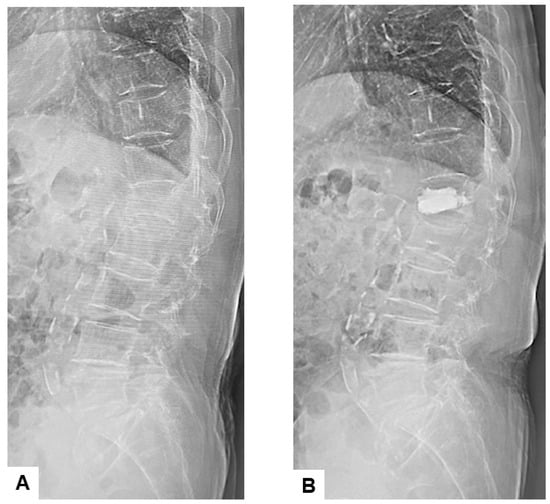

3.3. Radiographic Results